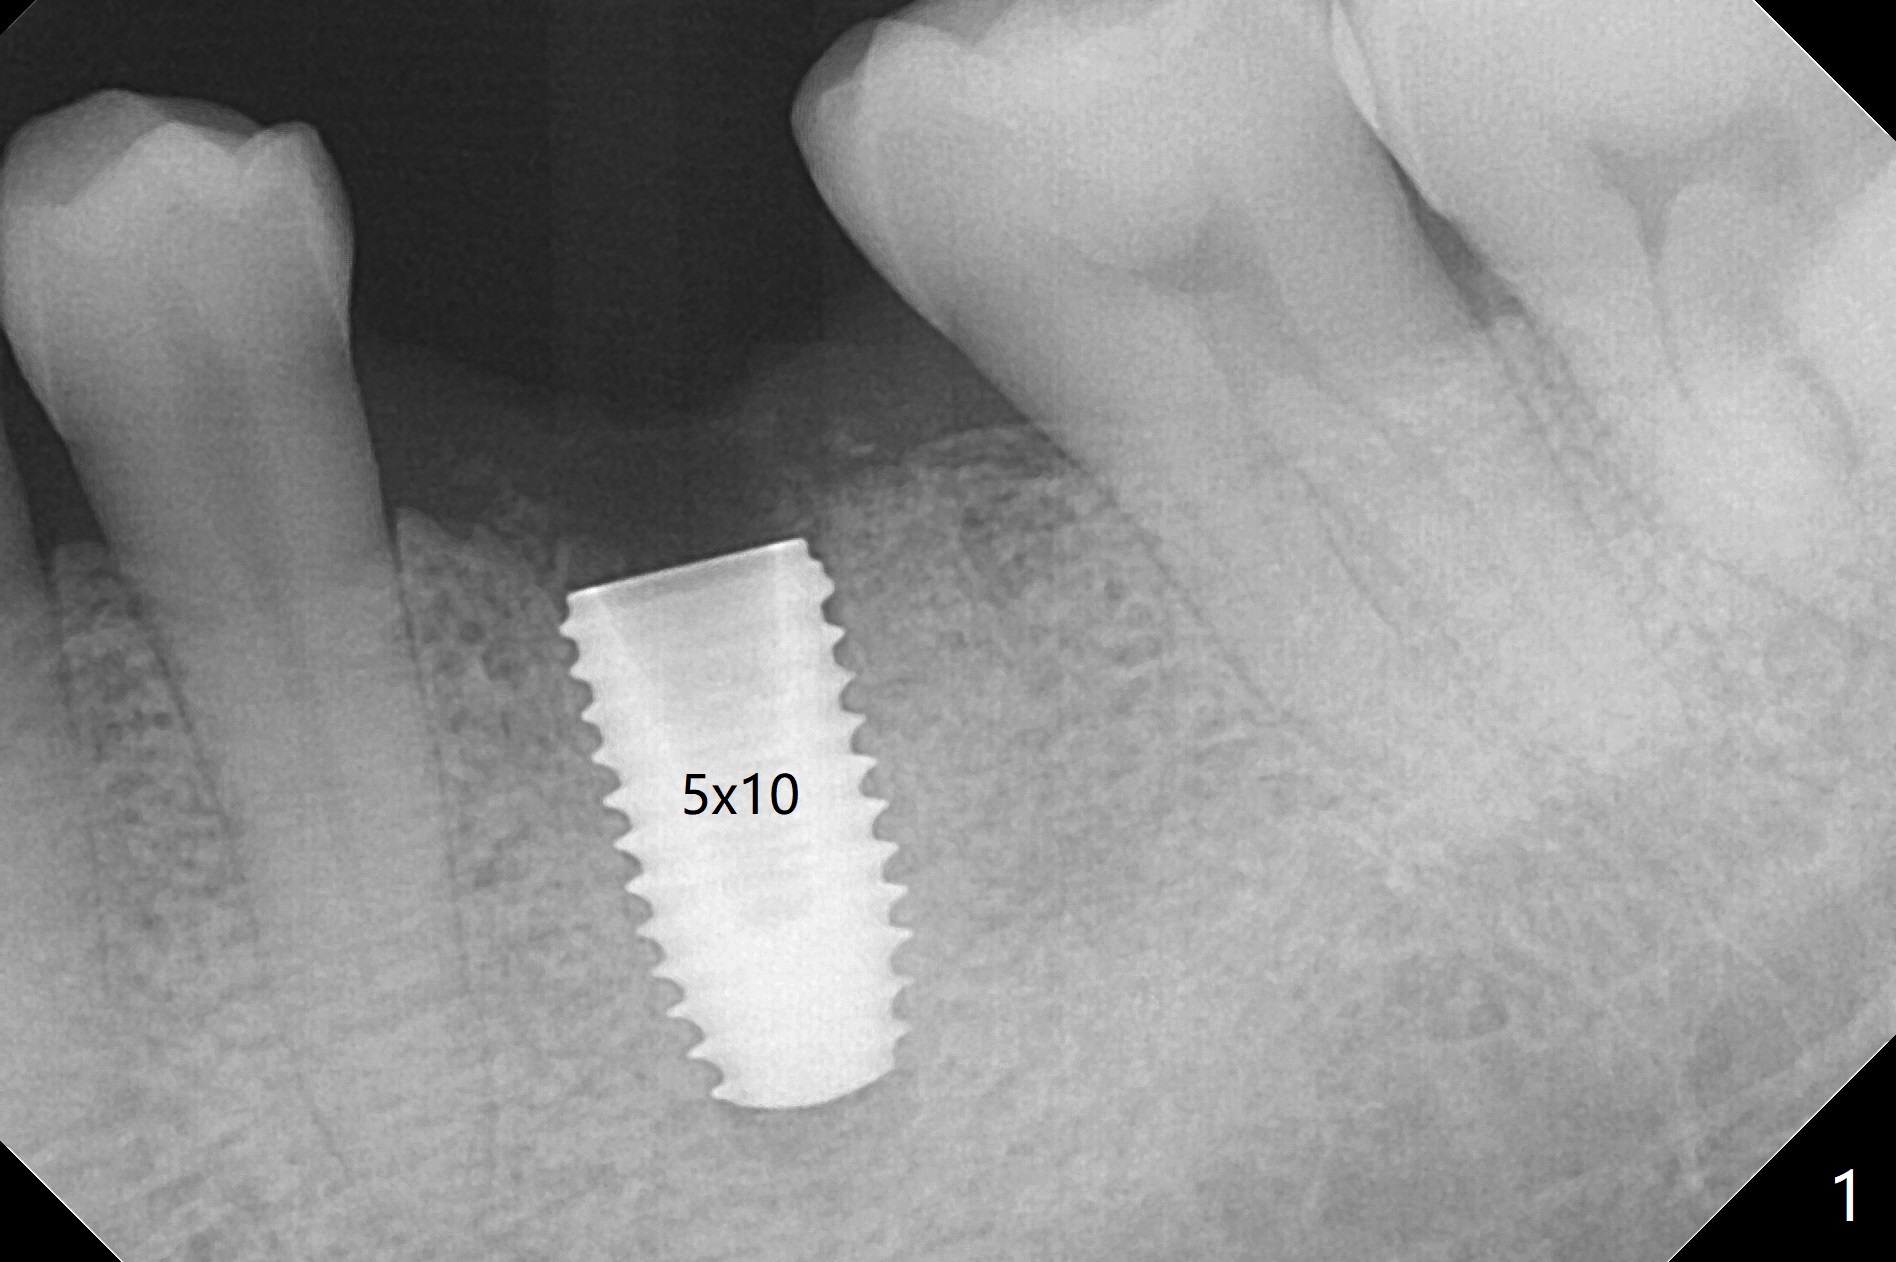

50来岁男,左下6位点保存术后4.5个月回来做导板植牙术,牙槽嵴和角化龈宽,几乎是最理想的手术。唯一担忧的是牙槽骨够不够硬(植骨后4.5个月),其实为了植入5毫米植体(图一),最后钻头必须4.5毫米,而且需要使用4.5毫米皮质骨功螺纹钻头,反复多次倒旋植体,最后扭力50Ncm,唯恐造成骨坏死。使用6毫米profile钻头后,放置6x4毫米基台,后者完全就位(图二,三)。术后病人汇报他根本感觉不到做过植牙术,以前做过徒手即刻植牙(30 13)。术后3.5月去除愈合基台,牙龈袖健康,使用Prosthetic treatment planning基台(没有六角形,容易就位,选择袖高度),放置修复基台(图四),拧紧20Ncm(厂家推荐30Ncm),放置plumber tape and Cavit,取模。口内粘固,事先牙冠(带有access hole)边缘涂凡士林,容易去除残余粘固剂,争取不取出基台,减少牙龈附着破坏。